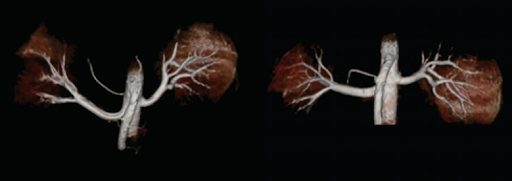

МРТ без контрастирования

В последнее время все больше внимания уделяется изучению потенциальных рисков, связанных с контрастными веществами на основе гадолиния. Технологии, позволяющие проводить полноценное МРТ-исследования без контраста, сводят к минимуму риск для пациентов с чувствительностью к веществам для контрастирования, при этом не снижая качество диагностики.

Технология Saturn

Технология Saturn от Canon Medical Systems обеспечивает более стабильное качество изображения благодаря повышенной стабильности градиента и точному контролю центральной частоты.

Диффузионно-взвешенное изображение с технологией PUREGradient